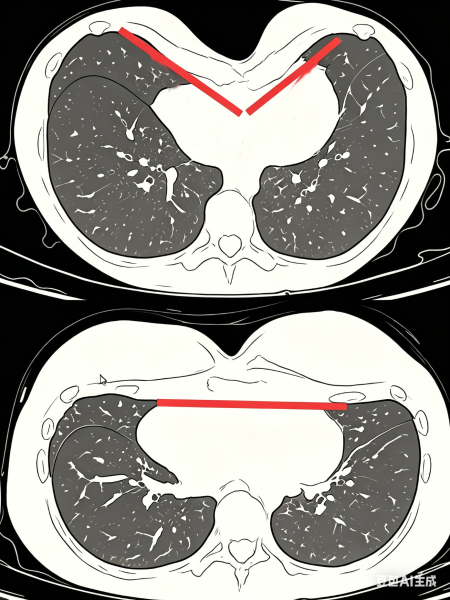

(图片来自AI,仅用于科普)

漏斗胸,学名叫 Pectus Excavatum,是胸廓最常见的先天性畸形。您可以简单理解为,孩子前胸壁的一部分骨骼和软骨,像搭“积木”一样,往里面“塌”下去了,导致外观上像一个凹陷的漏斗。它并非缺钙引起,单纯补钙、补铁并不能纠正漏斗胸;也不是睡姿不对,趴着睡背不了这个锅;更不是“缺心眼”,孩子们很聪明。

核心原因:连接胸骨和肋骨的肋软骨生长不均衡、过度生长,向前支撑不足,从而向后凹陷形成漏斗胸。它的存在有一定家族遗传倾向,如果家长幼时存在类似情况,孩子出现的概率会相对更高。

建议做一个CT检查,测量Haller指数(漏斗胸严重程度指数)。